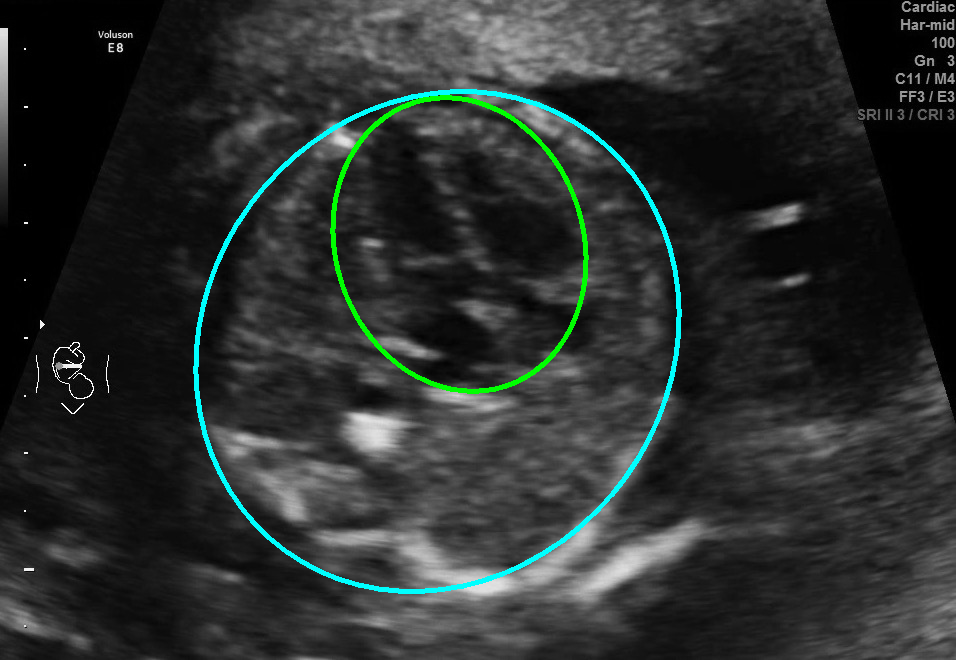

Visualization results of different methods.

Although the segmentation model trained on the fetal ultrasound dataset achieves a relative high average dice scores averaging over 0.9, the fitted ellipse highly depends on the segmentation results. As shown in the middle row of Fig. 2, the segment-based ellipse-fit method performs well when the image quality is good (first row), but the performance degrades when the segmentation is affected by image artifacts such as the acoustic shadowing (second and third row). Our proposed method is more robust to image quality and shadows. We also tried to compare to the GPN [9] with their open source code on our dataset, however, the results are not comparable to ours and those presented in Table. 1. It is difficult to conclude whether it is caused by the network itself or the training strategies. We, therefore, did not include the comparative results in this work.

As shown in Fig. 3 , both the proposed ellipse regression loss and IoU loss are necessary for ellipse detection. If the EllipseNet only supervised by IoU loss (first column), the model fails to optimize the major and minor axis separately, and the predicted ellipses degenerate into circles like the CircleNet. It is clear that the supervision of IoU loss can help to improve the prediction of location and shape (first and second row) and to correct the angle (last row).